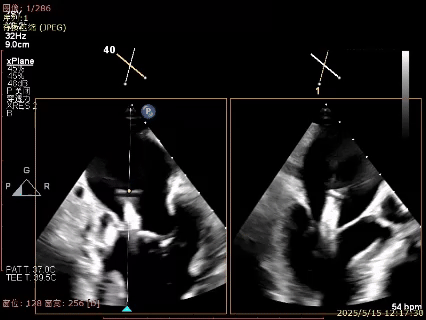

关紧夹子后上彩,反流降至轻度,内侧反流消失

XTR解脱后,XTR中间有轻度反流

DSA下可见两枚夹子活动稳固

术后肺静脉逆流消失

植入两枚夹子后二尖瓣平均跨瓣压差1mmHg